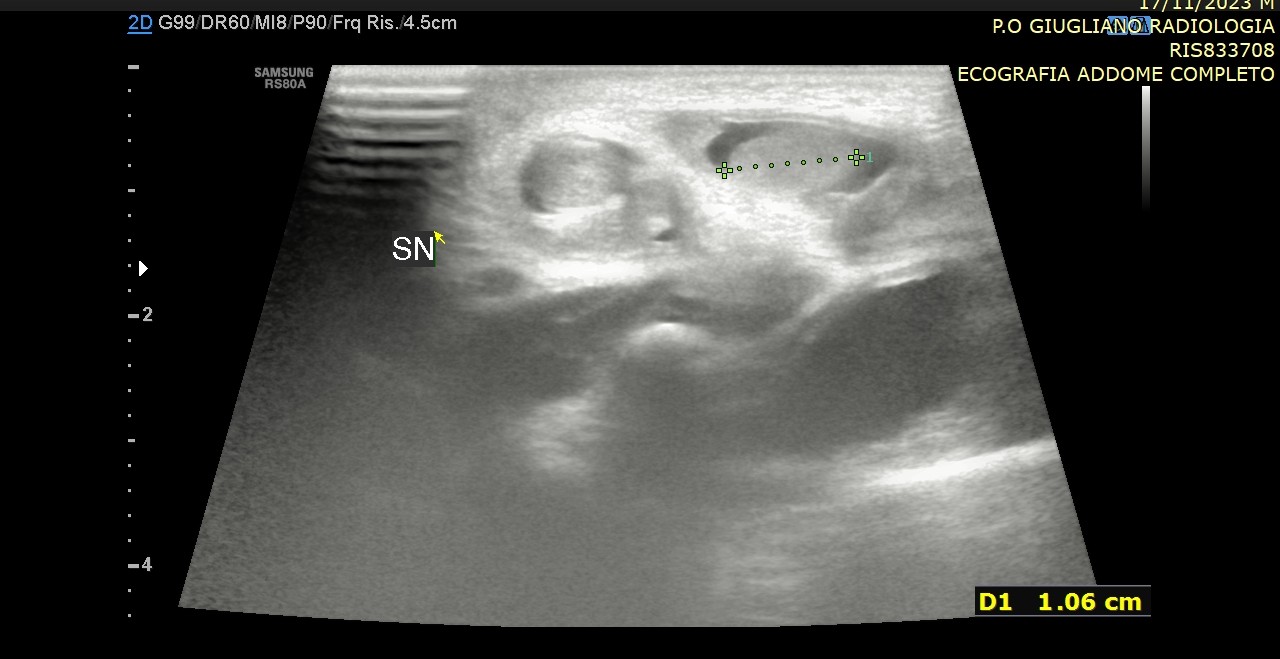

La diagnosi si basa innanzitutto sull’esame obiettivo del neonato o del bambino, affiancato quando necessario da indagini ecografiche o laparoscopiche. Il trattamento di scelta è chirurgico, tramite orchidopessi, e dovrebbe essere eseguito precocemente, idealmente tra i 6 e i 12 mesi di età, per ridurre al minimo i rischi futuri.